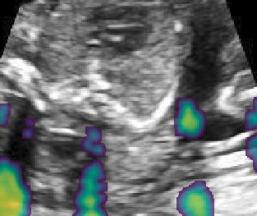

V-B Multi-view Image Fusion

Routine US screening is usually performed using a single 2D probe. However, the position of the probe and resulting tomographic view through the anatomy has great impact on diagnosis. Zimmer et al. [39] proposed a multi-view image reconstruction method, which compounds different images of the same anatomical structure acquired from different view directions. They use a Gaussian weighting strategy to blend intensity information from different views. Here, we combine predicted shadow confidence maps from these multi-view images as additional image fusion weights to investigate if these confidence maps can further improve image quality.

The proposed method generally outperforms the baseline and the proposedAG method, thus we only integrate the shadow confidence maps generated by the proposed method () into the weighting strategy in [39]. In detail, the probability value of each pixel in a shadow confidence map is multiplied to the original weight of the same pixel computed in [39]. The generated new weights are normalized as described in [39] and then are used for image fusion. The data set in this experiment is same as used for [39].

Fig. 9 qualitatively shows that shadow confidence maps are able to improve the performance of US image fusion algorithms with different weighting strategies. Fig. 9 also shows the difference between adding two different types of confidence maps. These two types of confidence maps are generated by the confidence estimation network which are separately trained by either MSE or Sigmoid loss. Fig. 9 (a) to (d) illustrate image fusion results for the same case using different combinations of weighting strategies and loss functions. The difference maps indicate that shadow confidence maps are capable of improving image fusion performance. Fig. 9 (e) to (h) show image fusion results on four different cases. We randomly select two positively affected cases (Fig. 9 (e) and (f)) to show visual improvement. We additionally show two randomly selected examples (Fig. 9 (g) and (h)) that don’t show perceptually significant improvements after adding shadow confidence maps. Quantitative evaluation for image fusion is not possible because of lacking a ground truth for US compounding tasks.

-G Examples for Image Fusion

Fig.15 shows more examples of the multi-view image fusion task which include the original multi-view images. From the column (a-b) of Fig.15, we can see that the original images contain strong shadow artifacts that can affect the anatomical analysis. The image fusion task aims to use complementary information from images with different views for reducing artifacts and increasing anatomical information. Column (e-f) enlarge the areas within the bounding boxes in column (c-d). Column (g) shows the difference masks between column (e)and (f). The difference masks clearly indicates the improved performance of image fusion after adding shadow confidence maps for Gaussian weighting strategy as well as Intensity and Gaussian weighting strategy.